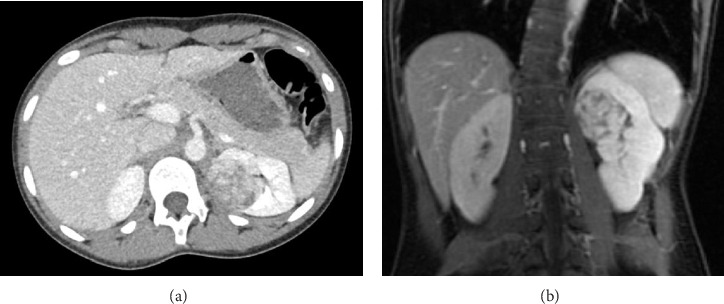

Juxtaglomerular cell tumor (JGCT), or reninoma, is a rare benign renal neoplasm. It is characterized by severe hypertension and hypokalemia due to excessive renin produced from the juxtaglomerular apparatus on the afferent arteriole of the glomerulus. Herein, we report a case of JGCT in a 15-year-old female who presented with severe hypertension. She was found to have elevated levels of renin and aldosterone with hypokalemia and she responded to angiotensin-converting enzyme inhibitors (ACEi). Abdominal MRI demonstrated a 4-cm left renal tumor. A radical nephrectomy was performed, and histology showed a well-circumscribed tumor consisting of sheets of polygonal to ovoid cells consistent with a JGCT. After surgery, the renin and aldosterone levels normalized, and blood pressure was controlled with small dose of ACEi medication. Unfortunately, the patient remained in Stage III chronic kidney failure due to the longstanding damage of uncontrolled hypertension prior to the diagnosis. We hereby review the literature and discuss the differential diagnosis.